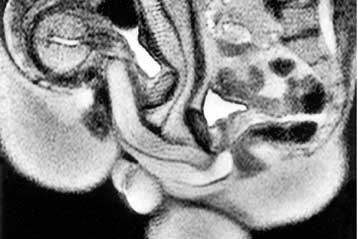

Ο εγκέφαλος των παχύσαρκων ανθρώπων είναι πρόωρα γερασμένος και σημαντικά μικρότερος σε σχέση με τα άτομα κανονικού βάρους, υποδεικνύει η πρώτη σύγκριση του είδους. Η παχυσαρκία συνδέεται με «σοβαρή εκφύλιση του εγκεφάλου» υποστηρίζουν οι ερευνητές.